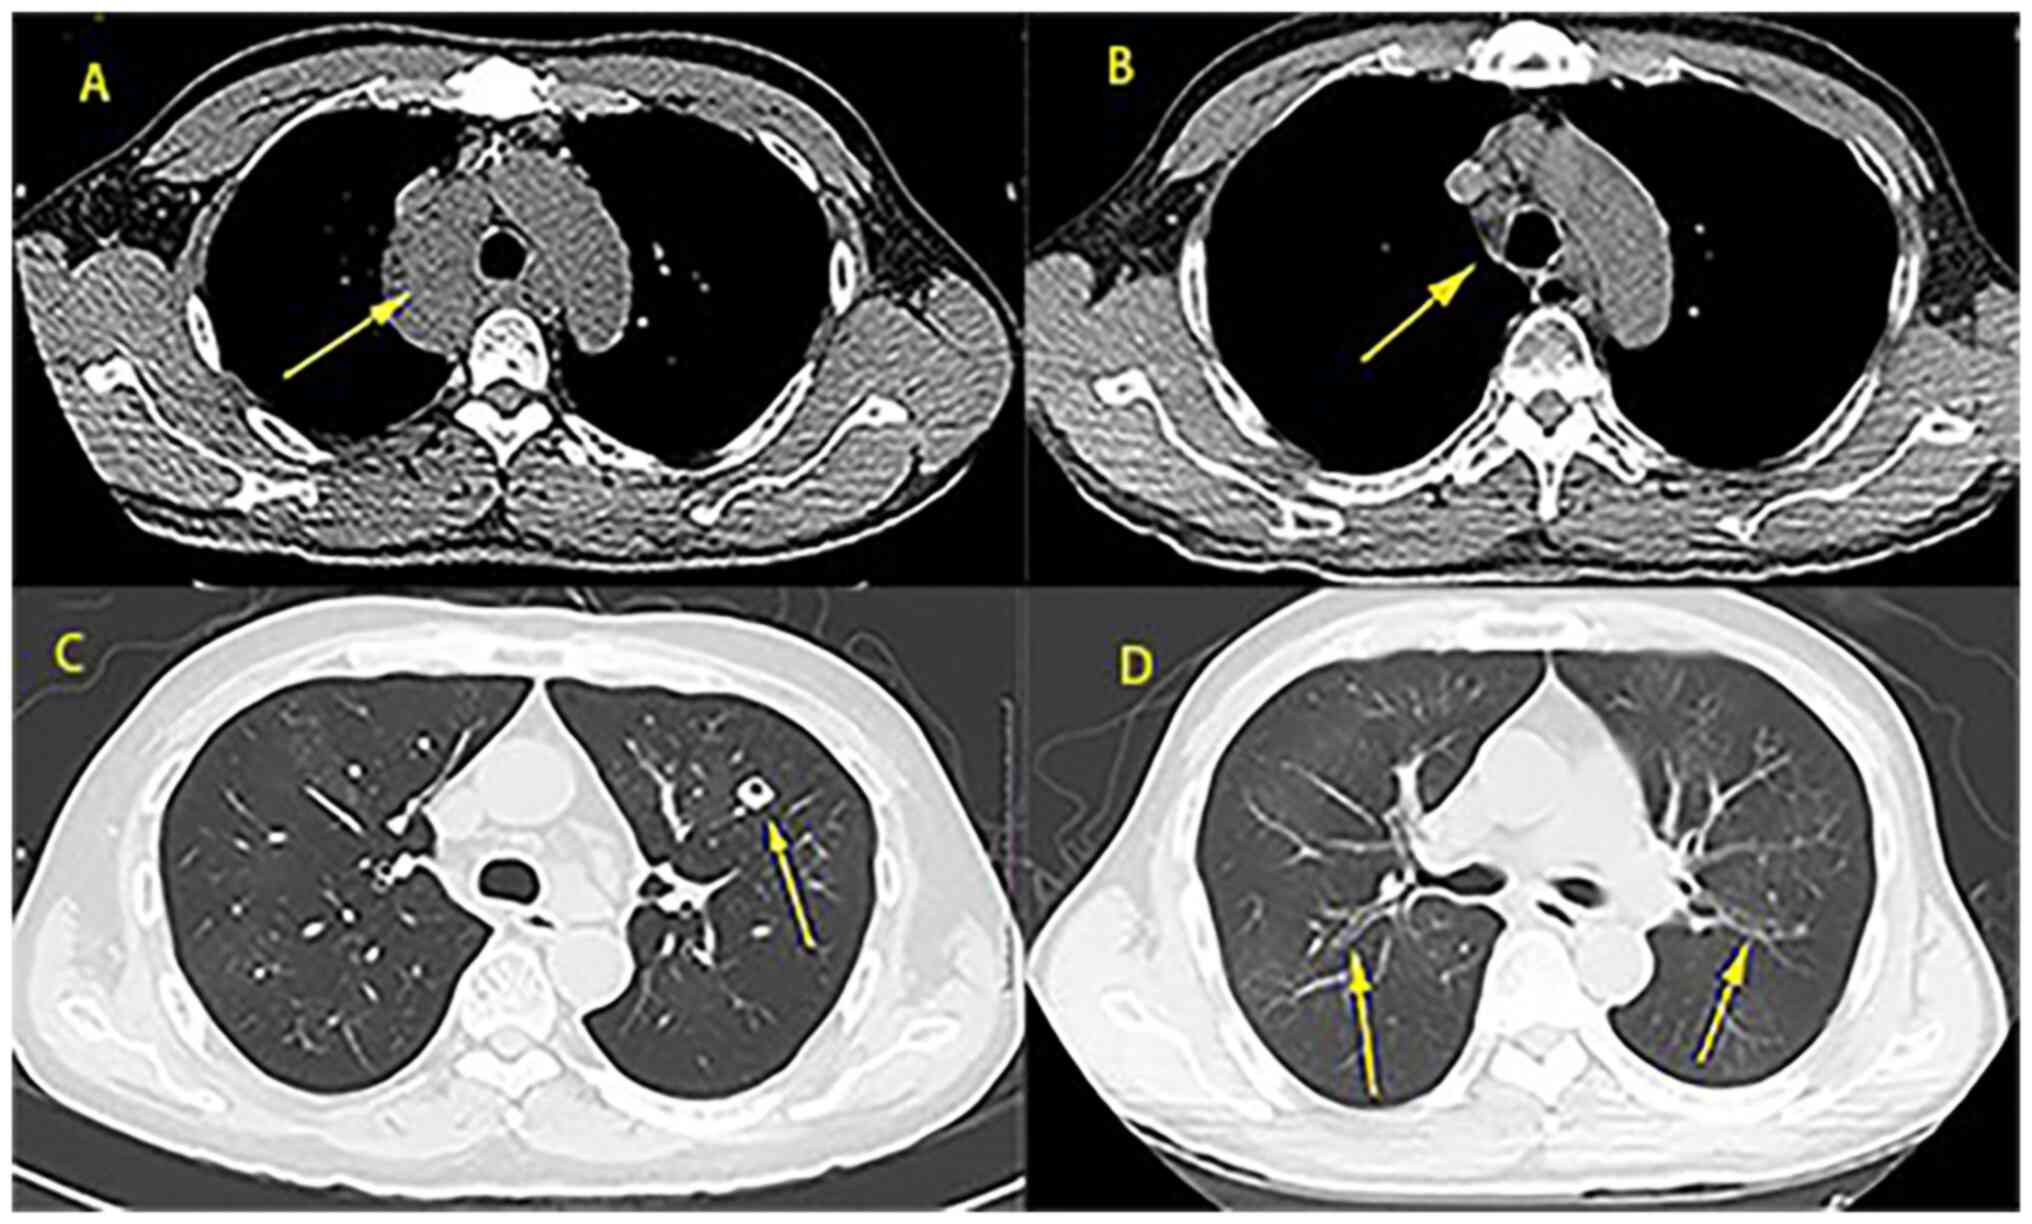

Multicentric Castleman disease of hyaline‑vascular variant with paraneoplastic pemphigus results in abnormal lung function: Report of 3 cases

Castleman disease (CD) is clinically divided into unicentric CD (UCD) and multicentric CD (MCD). Hyaline‑vascular variant (HV) is the most common pathological type of UCD, while the plasma cell type (PC) is the most common type of MCD and thus, hyaline‑vascular variant multicentric CD (HV‑MCD) is a rare type of CD. In addition, its etiology has remained elusive. The present study retrospectively analyzed the medical records of 3 patients diagnosed as HV‑MCD admitted to The First Affiliated Hospital of Guangxi Medical University (Guangxi, China) between January 2007 and September 2020. A total of 2 males and 1 female were admitted. The areas involved varied considerably. Respiratory symptoms were seen in 3 cases, along with fever, weight loss and splenomegaly. Damage to the skin and mucous membranes resulted in oral ulcers when accompanied by paraneoplastic pemphigus (PNP). Dry and wet rales were found in all patients. All 3 cases were complicated with PNP and had hypoxemia and obstructive ventilation dysfunction. In accordance with PC‑MCD, it manifested as lymph node enlargement and may involve several lymph nodes. Computed tomography mainly indicated bronchiectasis and mediastinal lymph node enlargement. In 1 case, chemotherapy failed after local mass excision, 1 case remitted after chemotherapy but the lung lesion was irreversible and 1 case was untreated and soon died of respiratory failure. The cases of HV‑MCD with pulmonary involvement were induced by small airway lesions and associated with poor prognosis. Respiratory symptoms along with systemic symptoms were common.

Figure 1

Figure 2

Figure 3

Figure 4